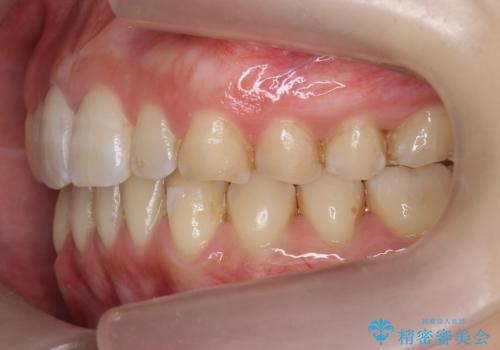

前歯のガタつき インビザラインで 下の前歯を1本抜歯

- 前歯のがたつきを主訴に来院。マウスピース矯正を希望されました。

治療にあたり、下の前歯を一本抜歯しています。

非抜歯で無理に治療をしようとすると、下の前歯の骨が薄く歯ぐきが下がったり、歯がぐらついたり、がたつきが完全にとれないリスクがあることを説明しました。

下の前歯が3本になるため、上下の正中は合わない仕上がりとなりますが、正中を合わせるには上下左右4本抜歯の上、ワイヤー矯正となってしまいます。

それよりは抜歯の数も少なく、メリットが大きいのではないかと説明し、選んでいただきました。

短期間できれいな歯並びになり、大変満足していただきました。